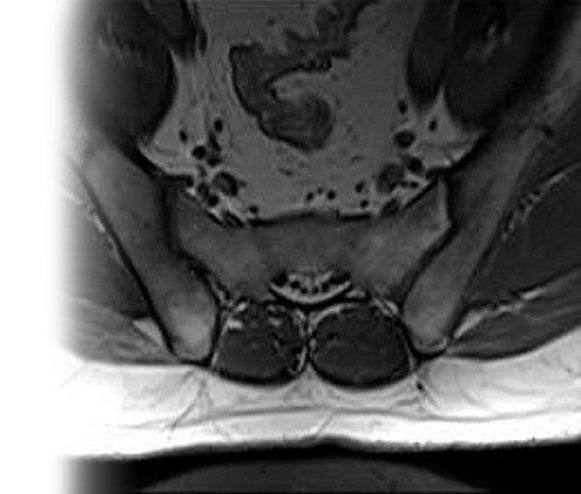

МРТ крестцово-подвздошных сочленений с контрастом

Магнитно-резонансная томография крестцово-подвздошных сочленений с контрастированием – важный метод исследования с введением контрастного вещества, которое позволяет визуализировать крестец, подвздошные кости, окружающие мягкие ткани.